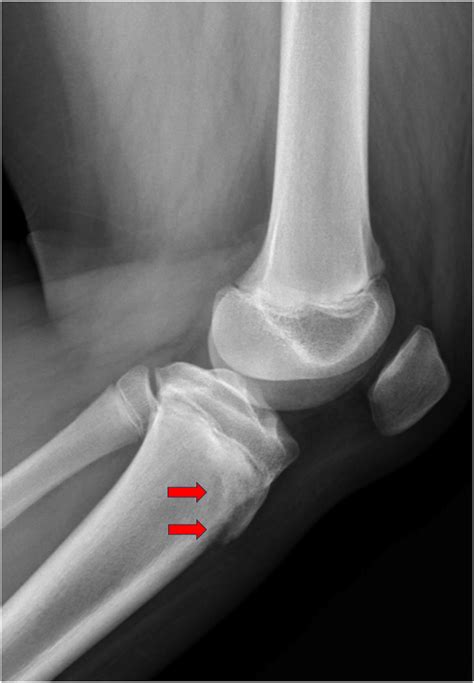

To confirm the diagnosis, medical professionals typically utilize imaging studies. X-rays are the gold standard for visualizing the displaced bone fragment and determining the severity of the fracture. In more complex or comminuted cases, an MRI may be ordered to assess the condition of the surrounding soft tissues, including the patellar tendon and menisci.

Immediate recognition of symptoms is crucial for effective treatment. Patients suffering from a Tibial Tuberosity Avulsion usually experience instantaneous, severe pain directly below the kneecap. The injury is often accompanied by a distinct "popping" sound or sensation at the time of impact.

• Deformity: A visible or palpable gap or bump may be present at the site of the injury.

Orthopedic surgeons often categorize these injuries based on the Ogden classification system, which helps guide treatment decisions. This classification ranges from simple, non-displaced fractures to complex injuries that extend into the knee joint.

Type I Small fracture at the distal part of the tuberosity. Conservative (casting)

Type II Fracture extends through the secondary ossification center. Surgery often required

Type III Fracture extends into the articular surface of the knee. Surgical intervention